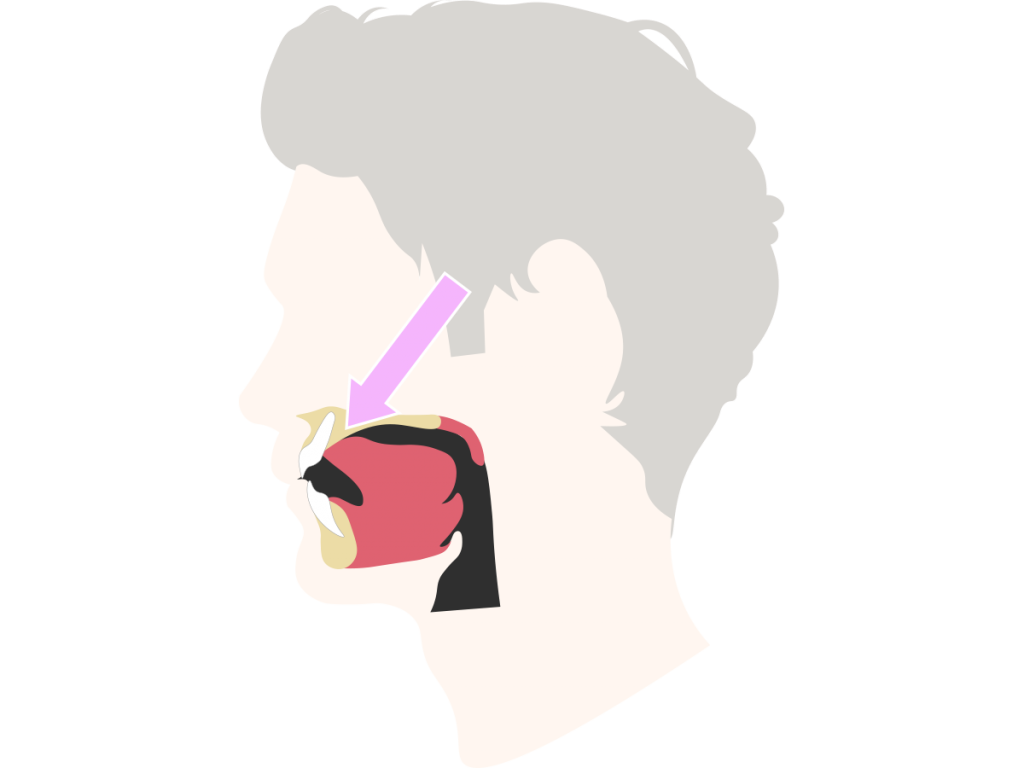

Am naheliegendsten ist dabei vermutlich die enge Beziehung zum Zungenbein. Die Hyoglossusmembran und das linguale Septum verbinden die Zunge wiederum mit den Zungenmuskeln. Die suprahyoidale (Muskeln oberhalb des Zungenbeins betreffend) Zungenaktion hilft nun, das Gleichgewicht und die Haltung des Kopfes zu stabilisieren.

Stellt euch barfuß auf ein Bein, die Zunge befindet sich im oberen Teil eures Mundes. Probiert das mit beiden Füßen. Wiederholt diese Übung nun, lasst eure Zunge diesmal aber im unteren Bereich eures Mundes ruhen. Und? Fällt euch etwas auf?

Der Unterschied, den ihr vermutlich wahrgenommen habt, hat damit zu tun, dass die Zunge in enger Beziehung zum zentralen und peripheren Nervensystem steht. Infolgedessen kann man mit der Zungenhaltung Einfluss auf die Arbeit von Gehirn und Rückenmark nehmen.

Interessant ist, dass sensorische Informationen von der Zunge über die Hirnnerven V, IX (N. glossopharyngeus) und X nicht, wie üblich, über den Hirnstamm im Gehirn verlaufen. Stattdessen werden sie auf der Ebene der oberen Halswirbelsäulensegmente über spezielle Neuronen weitergeleitet. Diese enge anatomische Verbindung lässt die Bewegungen der Zunge und die Bewegungen der Halswirbelsäule auf funktionelle Weise verschmelzen. „Dies ist besonders relevant bei manuellen medizinischen Behandlungen, bei denen die seitlichen Bewegungen der Zunge in der Mundhöhle in Verbindung mit der Bewegung der Halswirbelsäule therapeutisch genutzt werden können“ (Wagner, 2022). Auch kann dadurch nachvollzogen werden, warum Patienten bei Blockierungen der oberen HWS häufig ein Globusgefühl beklagen (ebd.).

Liegen sollte die Zunge jedoch auch nicht, da sich hieraus verschiedene Schmerzbeschwerden ergeben können, besonders im Nackenbereich und im Kiefer. Auch die Körperhaltung leidet und nicht zuletzt sogar die Ästhetik. Einfluss auf die Zungenposition hat wiederum die Atmung. Gibt es hierbei Probleme, ist zugleich auch das ausbalancierte Zusammenspiel der Zungenmuskeln gestört.

Die Antwort ist ganz einfach: Das vordere Zungendrittel ruht knapp hinter den oberen Schneidezähnen am Gaumen. Die Zungenspitze drückt dabei nicht gegen die Schneidezähne. Das ist die Zungenruheposition.